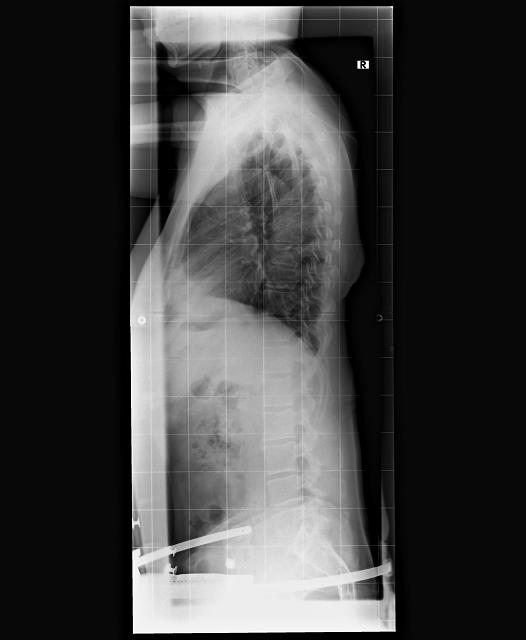

Anbei habe ich mal eine Grafik meiner Tragezeiten mit eingestellt.

- IMG_10042020_071508_(640_x_480_pixel).jpg (75.75 KiB) 13021 mal betrachtet